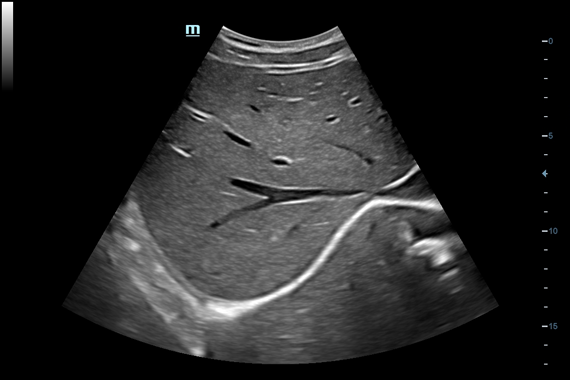

Система ультразвукового исследования Mindray DC-60 EXP X-INSIGHT является новейшей разработкой для проведения комплексных обследований на высшем уровне. Она обеспечивает решение самых сложных задач в таких областях, как кардиология, акушерство и гинекология, сосудистые заболевания, педиатрия и многие другие.

DC-60 EXP X-INSIGHT - это современный стационарный УЗИ-аппарат с функцией сенсорного управления и очищенной гармонической визуализацией, обеспечивающей лучшее контрастное разрешение и технологию 4D-визуализации. Он оснащен 21,5-дюймовым монитором, который может поворачиваться на 180 градусов, что удовлетворяет потребности врачей в качественной ультразвуковой диагностике.

Одним из ключевых преимуществ DC-60 EXP X-INSIGHT является технология формирования УЗ-луча. Она дополняет основной луч параллельно эхо-сигналами, что приводит к получению более мощного сигнала и изображений высокого качества с помощью систем iLive, iPage, Smart OB, Smart NT.